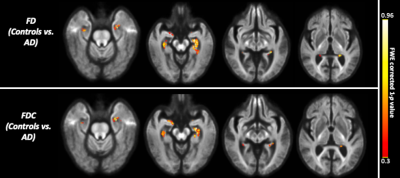

The whole-brain FBA showed significant reduction in FD in individuals with AD compared to MCI, in regions including splenium of corpus collosum, fornix, and the left uncinate fasciculus. Furthermore, AD showed significant reduction in FD in the left uncinate fasciculus compared to controls. Figure 2 shows WM tracts where significant (FWE corrected p <0.05) reductions in FD were observed.We observed subtle reduction in FD and FDC metrics (although the differences were not statistically significant after FWE corrections) in regions including corpus callosum (bilaterally), forceps majors (bilaterally), and uncinate fasciculus in AD compared to MCI. The reduction in FD was more pronounced compared to the reduction in FDC (Figure 3).Furthermore, FD and FDC were observed to be reduced (although not statistically significant after FWE correction) in regions including uncinate and the arcuate fasciculus (bilaterally) in AD relative to controls (Figure 4). We did not observe notable difference in FC in any groups. There were no reductions in FBA measures in MCI relative to controls.

Figure 3: Fibre tract-specific reductions in AD compared to MCI from whole-brain FBA. The white matter regions showing subtle (statistically not significant after FWE correction) to significant reductions in FD, and FDC are superimposed onto the population template.

Figure 4: Fibre tract-specific reductions in AD compared to controls from whole-brain FBA. The white matter regions showing subtle (statistically not significant after FWE correction) to significant reductions in FD, and FDC are superimposed onto the population template.